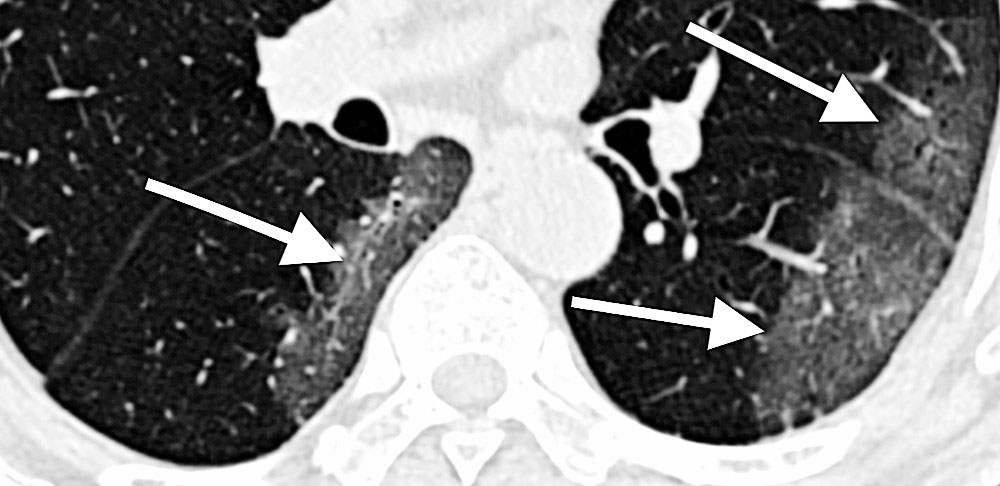

The features of infected lungs and hearts seen on medical images can help assess disease severity, predict response to treatment, and improve patient outcomes. However, a major challenge is to rapidly and accurately identify these signatures and evaluate this information in combination with many other clinical symptoms and tests. The MIDRC goals are to lead the development and implementation of new diagnostics, including machine learning algorithms, that will allow rapid and accurate assessment of disease status and help physicians optimize patient treatment.

“This effort will gather a large repository of COVID-19 chest images,” explained Guoying Liu, Ph.D., the NIBIB scientific program lead on this effort, “allowing researchers to evaluate both lung and cardiac tissue data, ask critical research questions, and develop predictive COVID-19 imaging signatures that can be delivered to healthcare providers.”